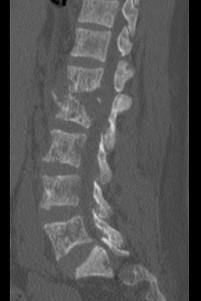

问题 男,67岁,背痛,发热,寒战半月余,有镰状细胞贫血病,请结合影像学检查,选择最可能的诊断 ( )

选项 A、脊髓空洞症 B、脊柱骨髓炎 C、椎体压缩骨折 D、脊柱转移瘤 E、脊柱结核

答案 B